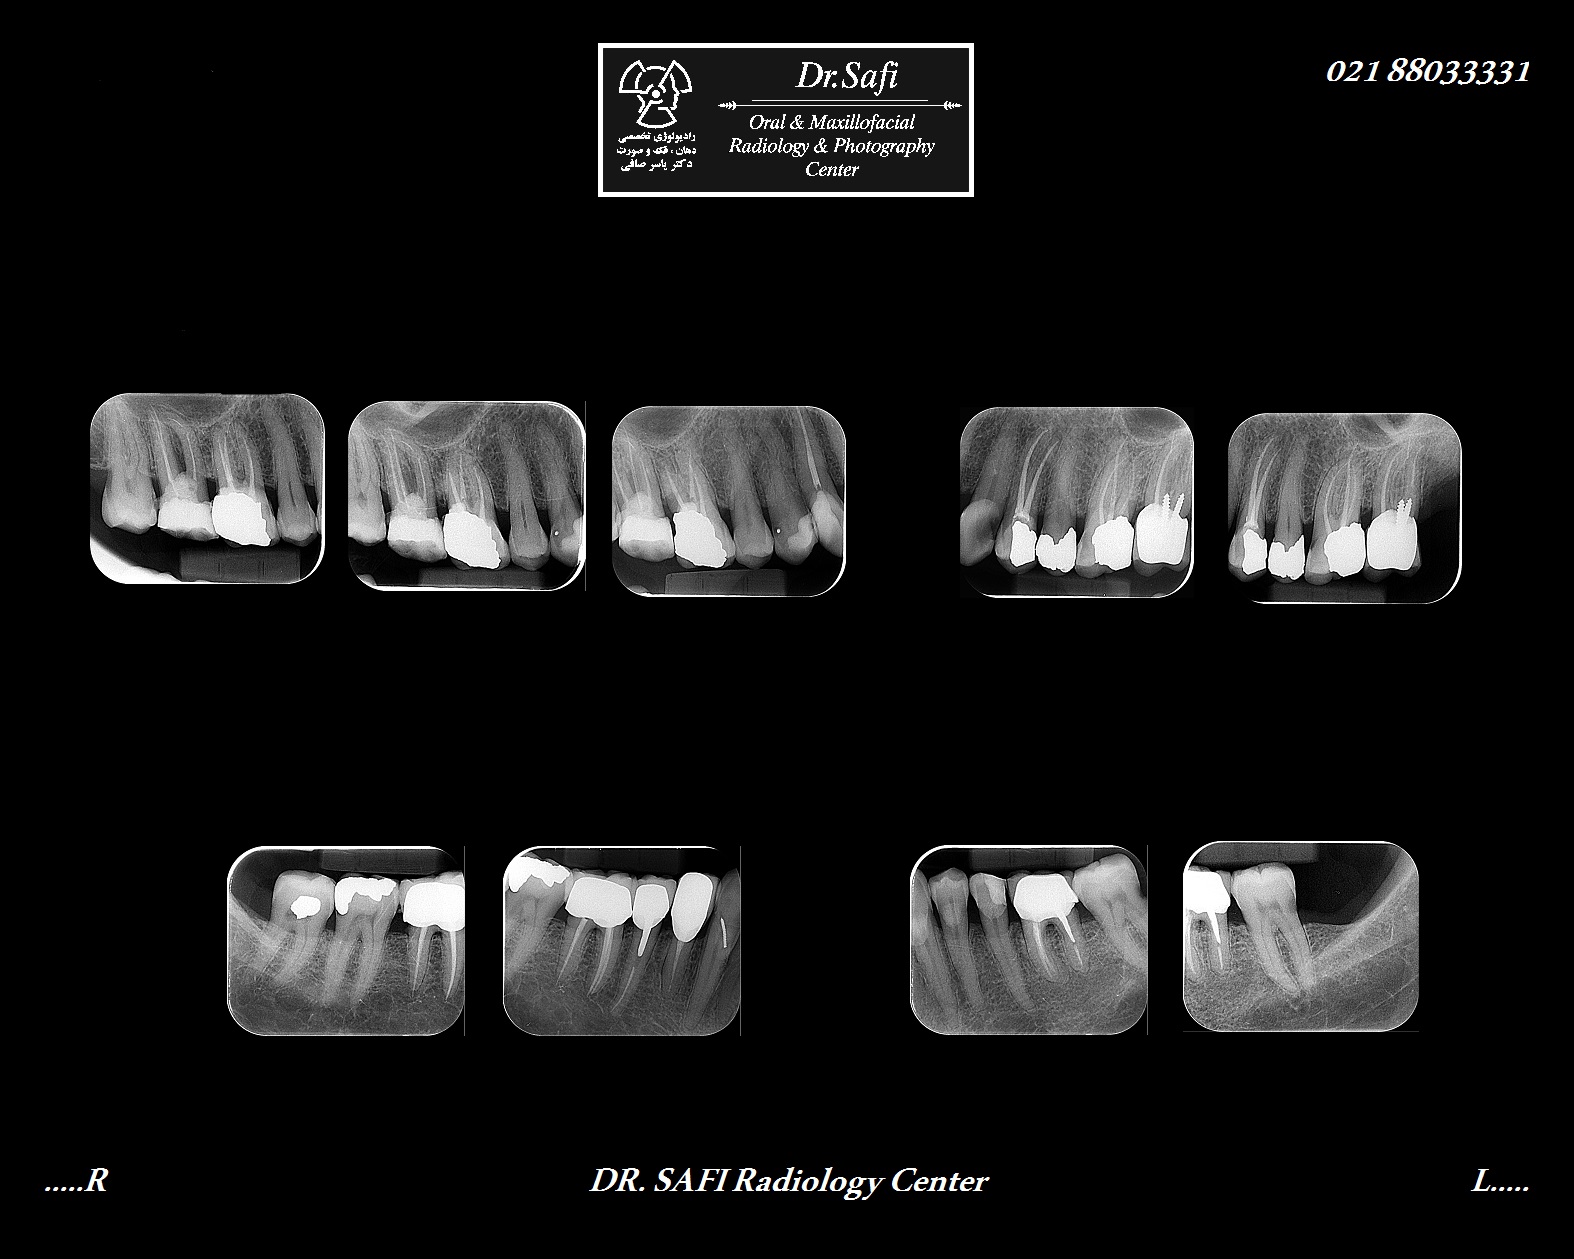

رادیوگرافی پری اپیکال (Periapical) (PA)

رادیوگرافی پری اپیکال تکنیکی داخل دهانی جهت بررسی تک دندان و بافت های اطراف آن می باشد. هر کلیشه نشان دهنده ویژگی ها و جزئیات دندان و استخوان آلوئولار می باشد. از جمله مهم ترین مشخصه های بالینی موجود در رادیوگرافی پری اپیکال عبارتند از:

• ارزیابی و تشخیص پوسیدگی های دندانی

• ارزیابی وضعیت بافت اطراف دندان

• ارزیابی وضعیت دندان و استخوان آلوئولار اطراف آن پس از تروما

• ارزیابی وضعیت و موقعیت دندان های نهفته

• ارزیابی مورفولوژی ریشه دندان و کانال های آن

• ارزیابی قبل و بعد از جراحی اپیکال

• ارزیابی دقیق کیست های اپیکال و سایر ضایعات مرتبط با استخوان آلوئولار

• ارزیابی وضعیت ایمپلنت

• ارزیابی عفونت و یا التهاب بخش اپیکال دندانی

جهت انجام عکس برداری دقیق نحوه قرارگیری کلیشه، نگه دارنده و منبع پرتو بسیار حائز اهمیت می باشد. از آنجاییکه آناتومی حفره دهانی در افراد مختلف متفاوت می باشد، جهت دستیابی به نتایج بهتر، دو تکنیک در انجام عکس برداری پری اپیکال مورد استفاده قرار می گیرد که عبارتند از:

• تکنیک موازی یا Parallel

• تکنیک نیمساز یا Bisect

با توجه به اینکه تکنیک موازی به دلیل ژئومتری فیلم، دندان و اشعه ایکس ایده آل است، در رادیولوژی تخصصی دکتر صافی همواره از تکنیک موازی استفاده می شود.